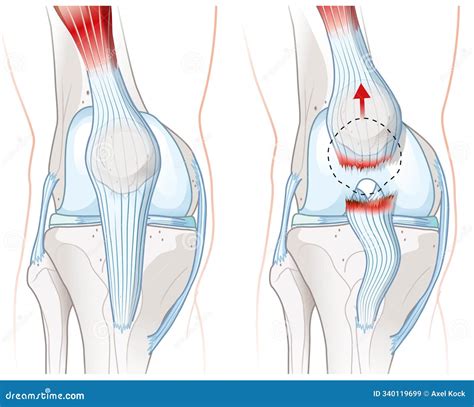

• Sudden, Severe Pain: A sharp, intense pain in the front of the knee, often described as a “pop” or “tear” sensation.

• Inability to Straighten the Knee: Difficulty or inability to fully extend the knee, often due to a gap in the tendon.

• Palpable Gap: A visible or palpable gap in the tendon, which can be felt just below the patella.